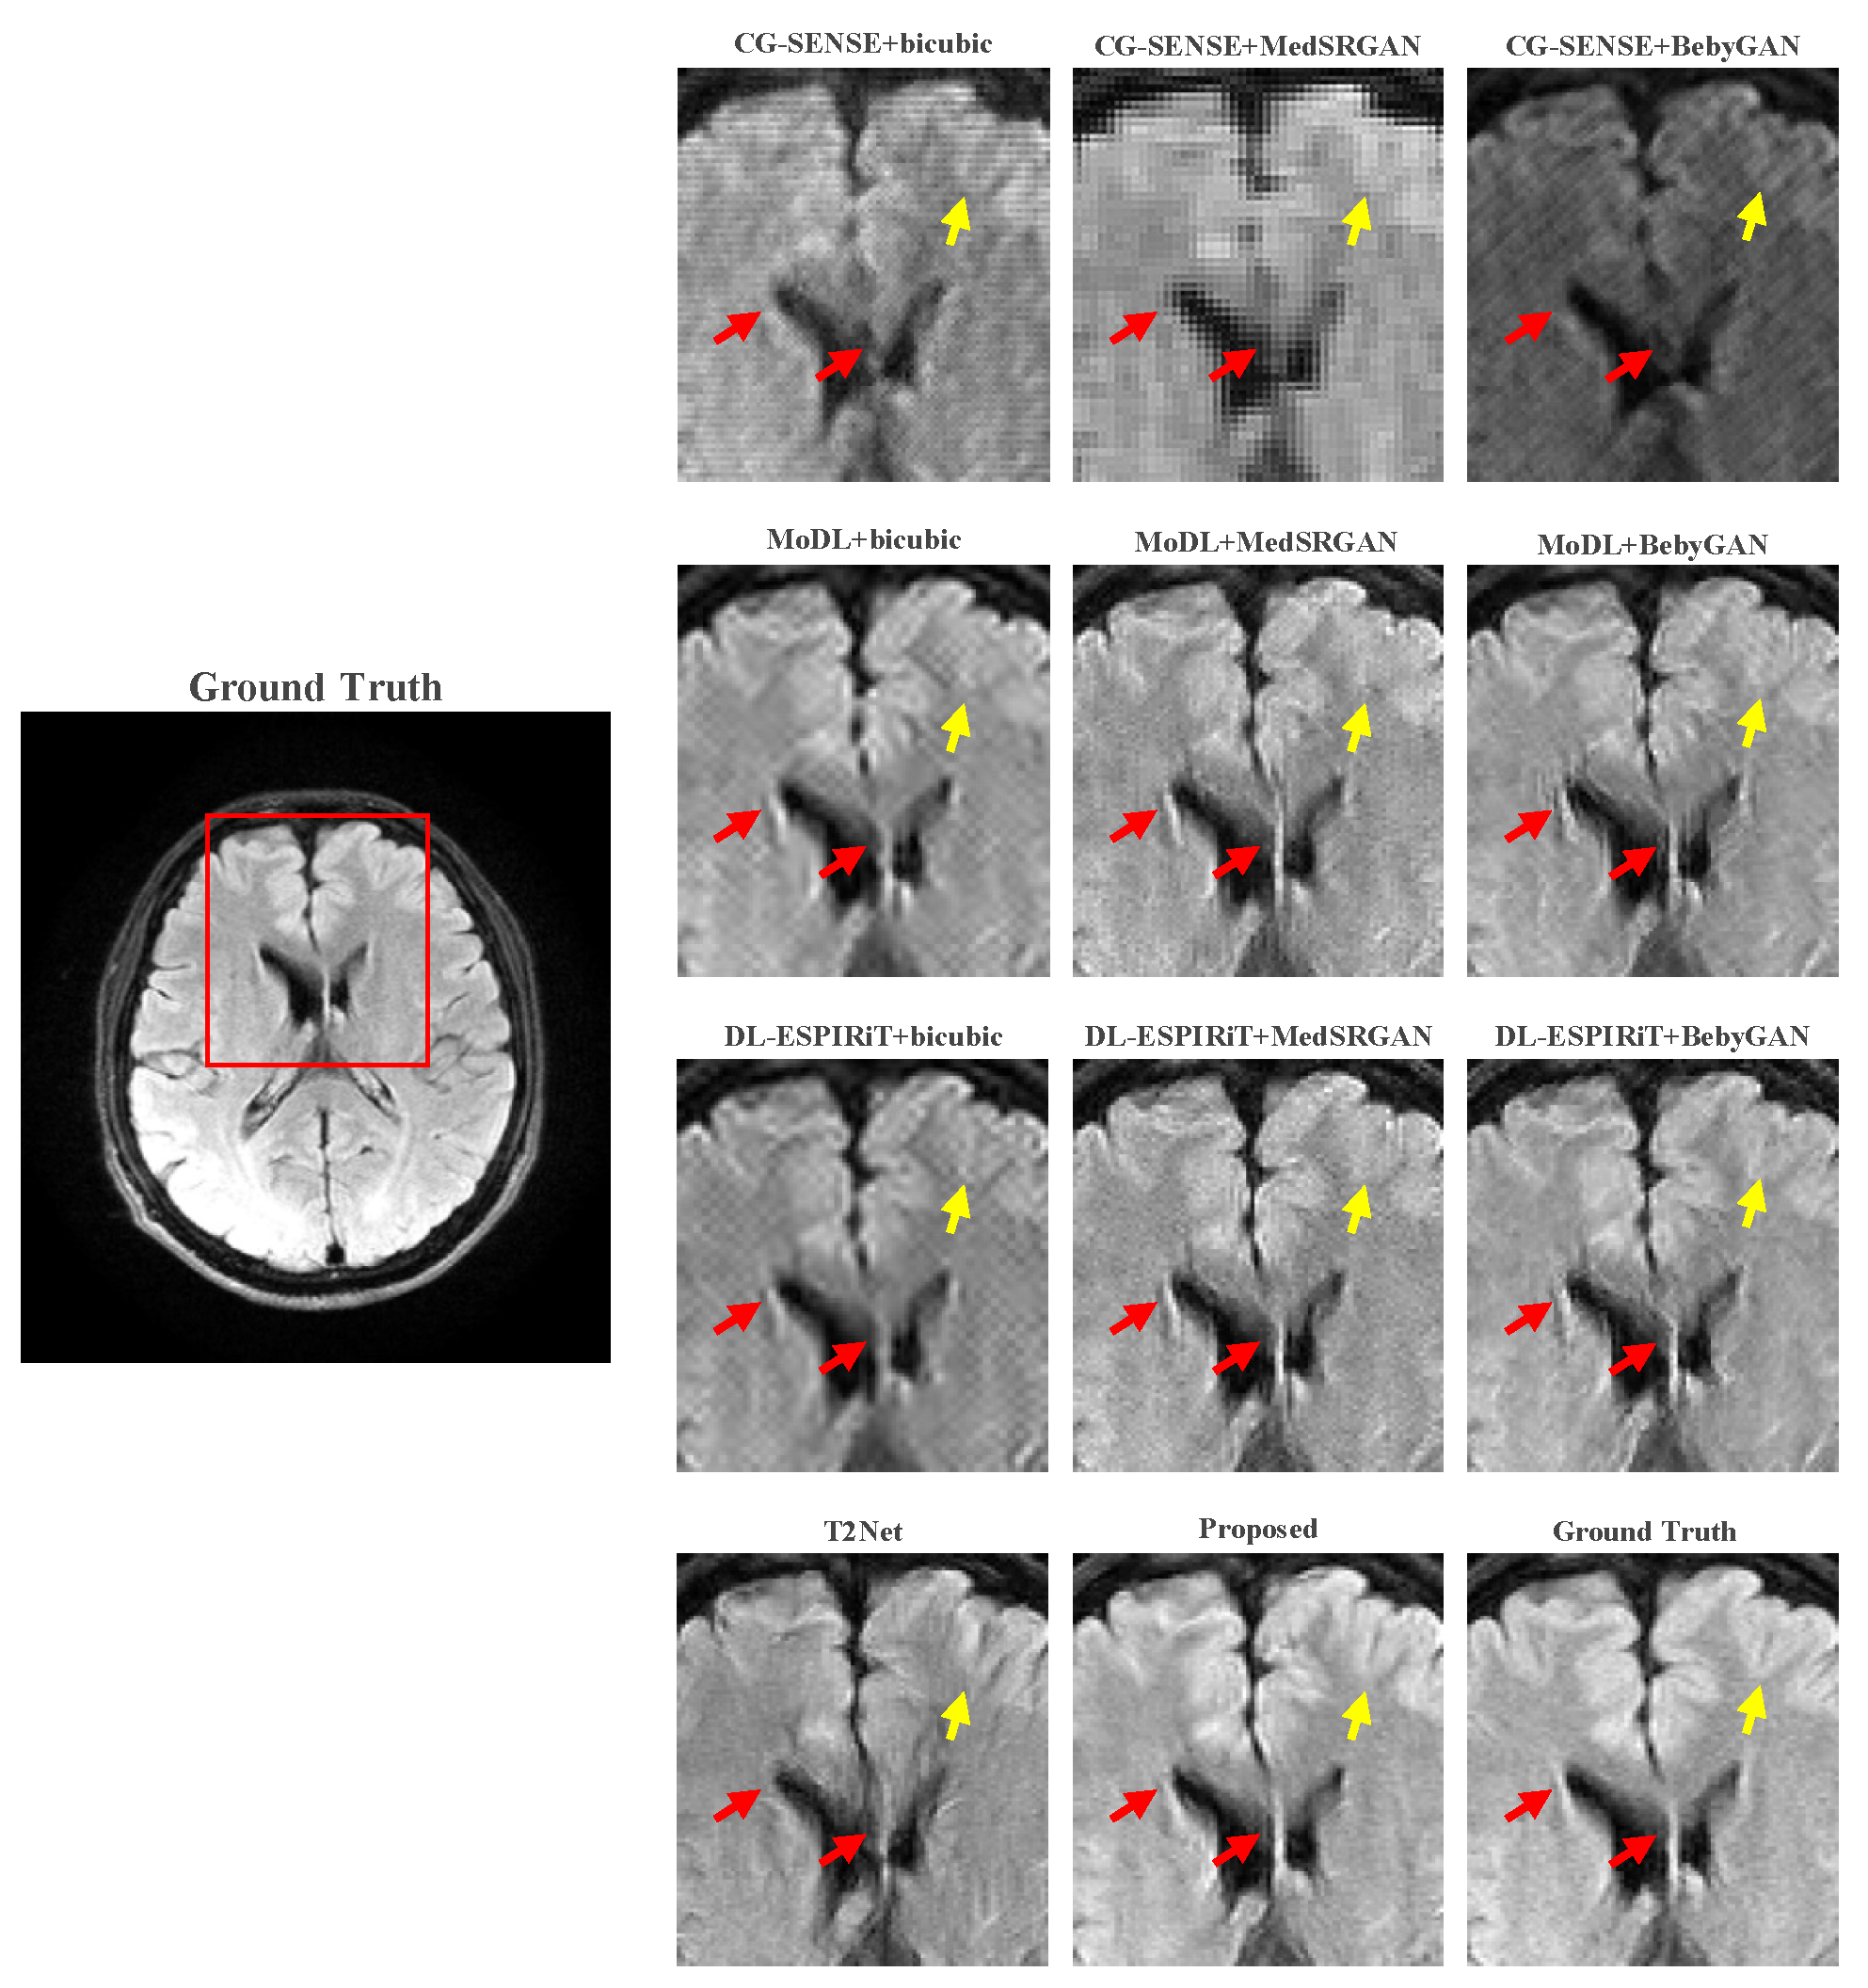

For a more intuitive comparison, we provide visual comparisons for each method. In Figure 5 and Figure 6, we illustrate the axial and sagittal views of the 2D brain dataset, respectively. In Figure 7 and Figure 8, we display the brain image and neck image of the 3D VWI dataset. For each method, we show the restorations along with the corresponding error maps. The images are placed on the left, the error maps on the right, and the PSNR and LPIPS metrics of each image are shown at the bottom right corner. From the error maps, it is evident that our proposed method consistently produces high-quality results with improved visual fidelity and better retention of structural information compared to the other methods.

Figure 9 and Figure 10 present the zoomed-in images of the enclosed parts in the ground truth. Our proposed method can faithfully recover the fine structures, as indicated by the red arrows, and successfully preserve the image contrast, as pointed out by the yellow arrow. The high-fidelity restoration achieved by our method in these zoomed-in regions further demonstrates its ability to faithfully recover fine details and enhance image quality.

Figure 9. Zoomed-in view of the brain dataset comparison experiment.

Bioengineering 10 01107 g009